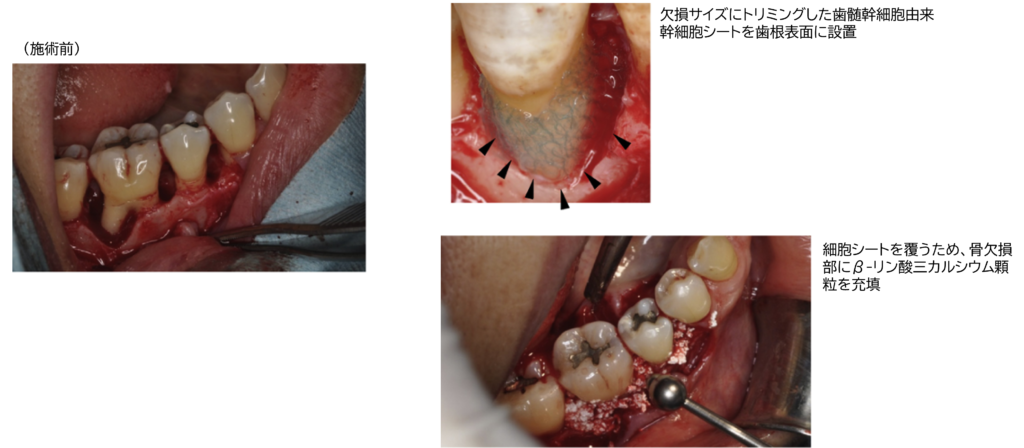

このような歯周炎の病態に対し、CTTが研究開発を進める「歯根膜由来幹細胞シート」は、再生医療の新たな選択肢として注目されています。この細胞シートは、歯根膜由来の幹細胞を培養し、骨形成を促進するサイトカイン(例:BMP-2、VEGFなど)を産生・分泌する能力を有しています。移植後は歯根膜として患部に定着し、歯根膜本来の構造的・機能的特性を発揮することで、歯槽骨の再生を誘導し、歯周組織全体の修復を促進します。

こうした状況を踏まえ、CTTは、細胞シート技術の応用可能性を拡張すべく、新たな製品「歯根膜テープ」の開発を推進しています。この製品は、他家由来の歯根膜幹細胞を用いた培養技術をベースに設計されており、再生医療の中でも特に歯科・口腔領域における治療ニーズに応えることを目的としています。

歯根膜テープは、細胞シートの利点(高い細胞密度、組織接着性、局所的な生理活性)を活かしながら量産性と価格適正化を重視した設計がなされており、より多くの患者がアクセス可能な治療選択肢としての社会実装を目指しています。